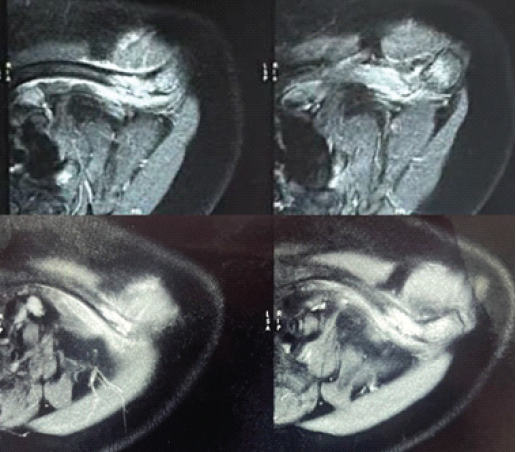

Computed tomography scans were consistent with features of “giant cell tumor” and magnetic resonance imaging reported the possibility of “metastasis” or “multiple myeloma” (Figs. 2 and 3).

Figure 2: T2-weighted magnetic resonance imaging left shoulder: showing an expansile, fluid-filled, and lytic lesion in the mid-shaft of the clavicle with pathological fracture and surrounding soft-tissue edema.